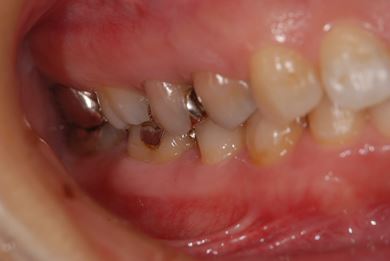

抜歯即日スピードインプラント治療+セラミック治療+歯肉歯槽骨整形術

| 性別/年齢 | 女性 / 39歳 | ||||||||||||||||||||||||||||||||

| 主訴 | 銀歯が取れたのでみて欲しい。 | ||||||||||||||||||||||||||||||||

| 治療方針 | 左下欠損部と保存不能の歯を抜歯し、インプラント治療にて機能的・審美的回復を行う。 | ||||||||||||||||||||||||||||||||

| 治療内容 | インプラント2本(抜歯即日スピードインプラント)、ハイブリッドセラミッククラウン2本、歯肉歯槽骨整形術 | ||||||||||||||||||||||||||||||||

| 総治療費 | 488,250円 | ||||||||||||||||||||||||||||||||

| 治療期間 | 1年4ヶ月 |